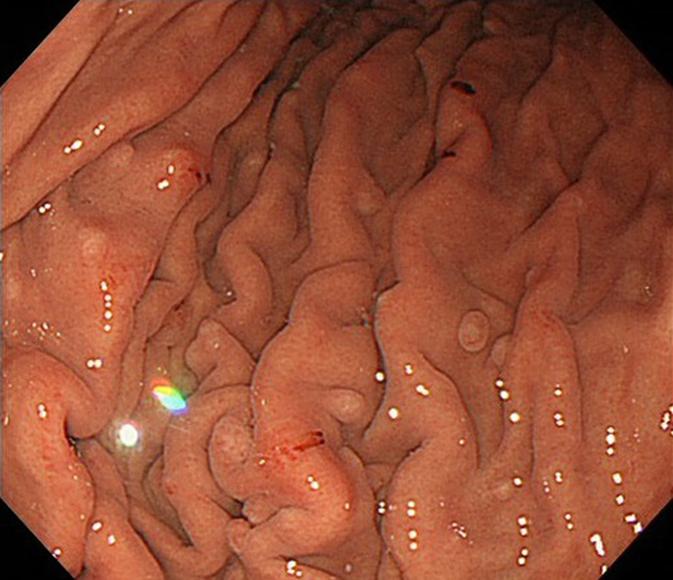

We describe the case of a man with fundic gland polyposis associated with proton-pump inhibitor (PPI) use. Some investigators have reported an association between long-term PPI use and an increase in the risk of developing fundic gland polyps (FGPs). These FGPs are considered to be reversible on stopping PPI treatment. The current patient had used a PPI for 10 years, resulting in multiple FGPs in his gastric body. However, 6 months after cessation of the PPI, the FGPs had obvously regressed, even though a histamine-2 receptor antagonist had subsequently been prescribed. This case demonstrates a link between PPI treatment and FGPs.

我们描述了一例患有与质子泵抑制剂(PPI)使用相关的胃底腺息肉病的男性病例。一些研究人员报告了长期使用PPI与胃底腺息肉(FGP)发生风险增加之间的关联。这些FGP被认为在停止PPI治疗后是可逆的。该患者使用PPI达10年,导致胃体部出现多个FGP。然而,在停用PPI 6个月后,尽管随后开具了组胺-2受体拮抗剂,但FGP明显消退。该病例证明了PPI治疗与FGP之间的联系。